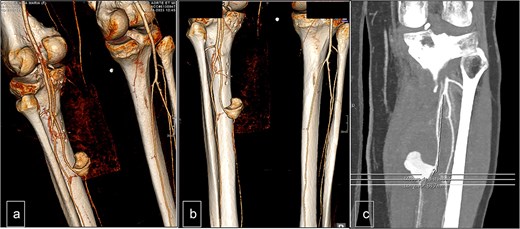

The patient underwent follow-up assessments at 3 weeks and 3 months, which showed an uneventful recovery. Postoperative Doppler sonography demonstrated normal physiological flow (Fig. 4).

Postoperative duplex sonography. (a) Doppler mode. Identification of the PTA. (b) Doppler mode. Triphasic physiological flow in distality of the autologous patch. (c) Doppler mode. Permeability of the PTA.